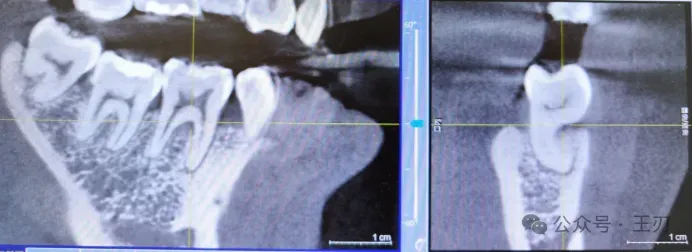

同样的,17的远中根据探诊结果有牙周深袋,将视图拉到舌侧(上图),可以看到17远中有明显的骨吸收,而将视图拉到颊侧(下图),看不到明显骨吸收。